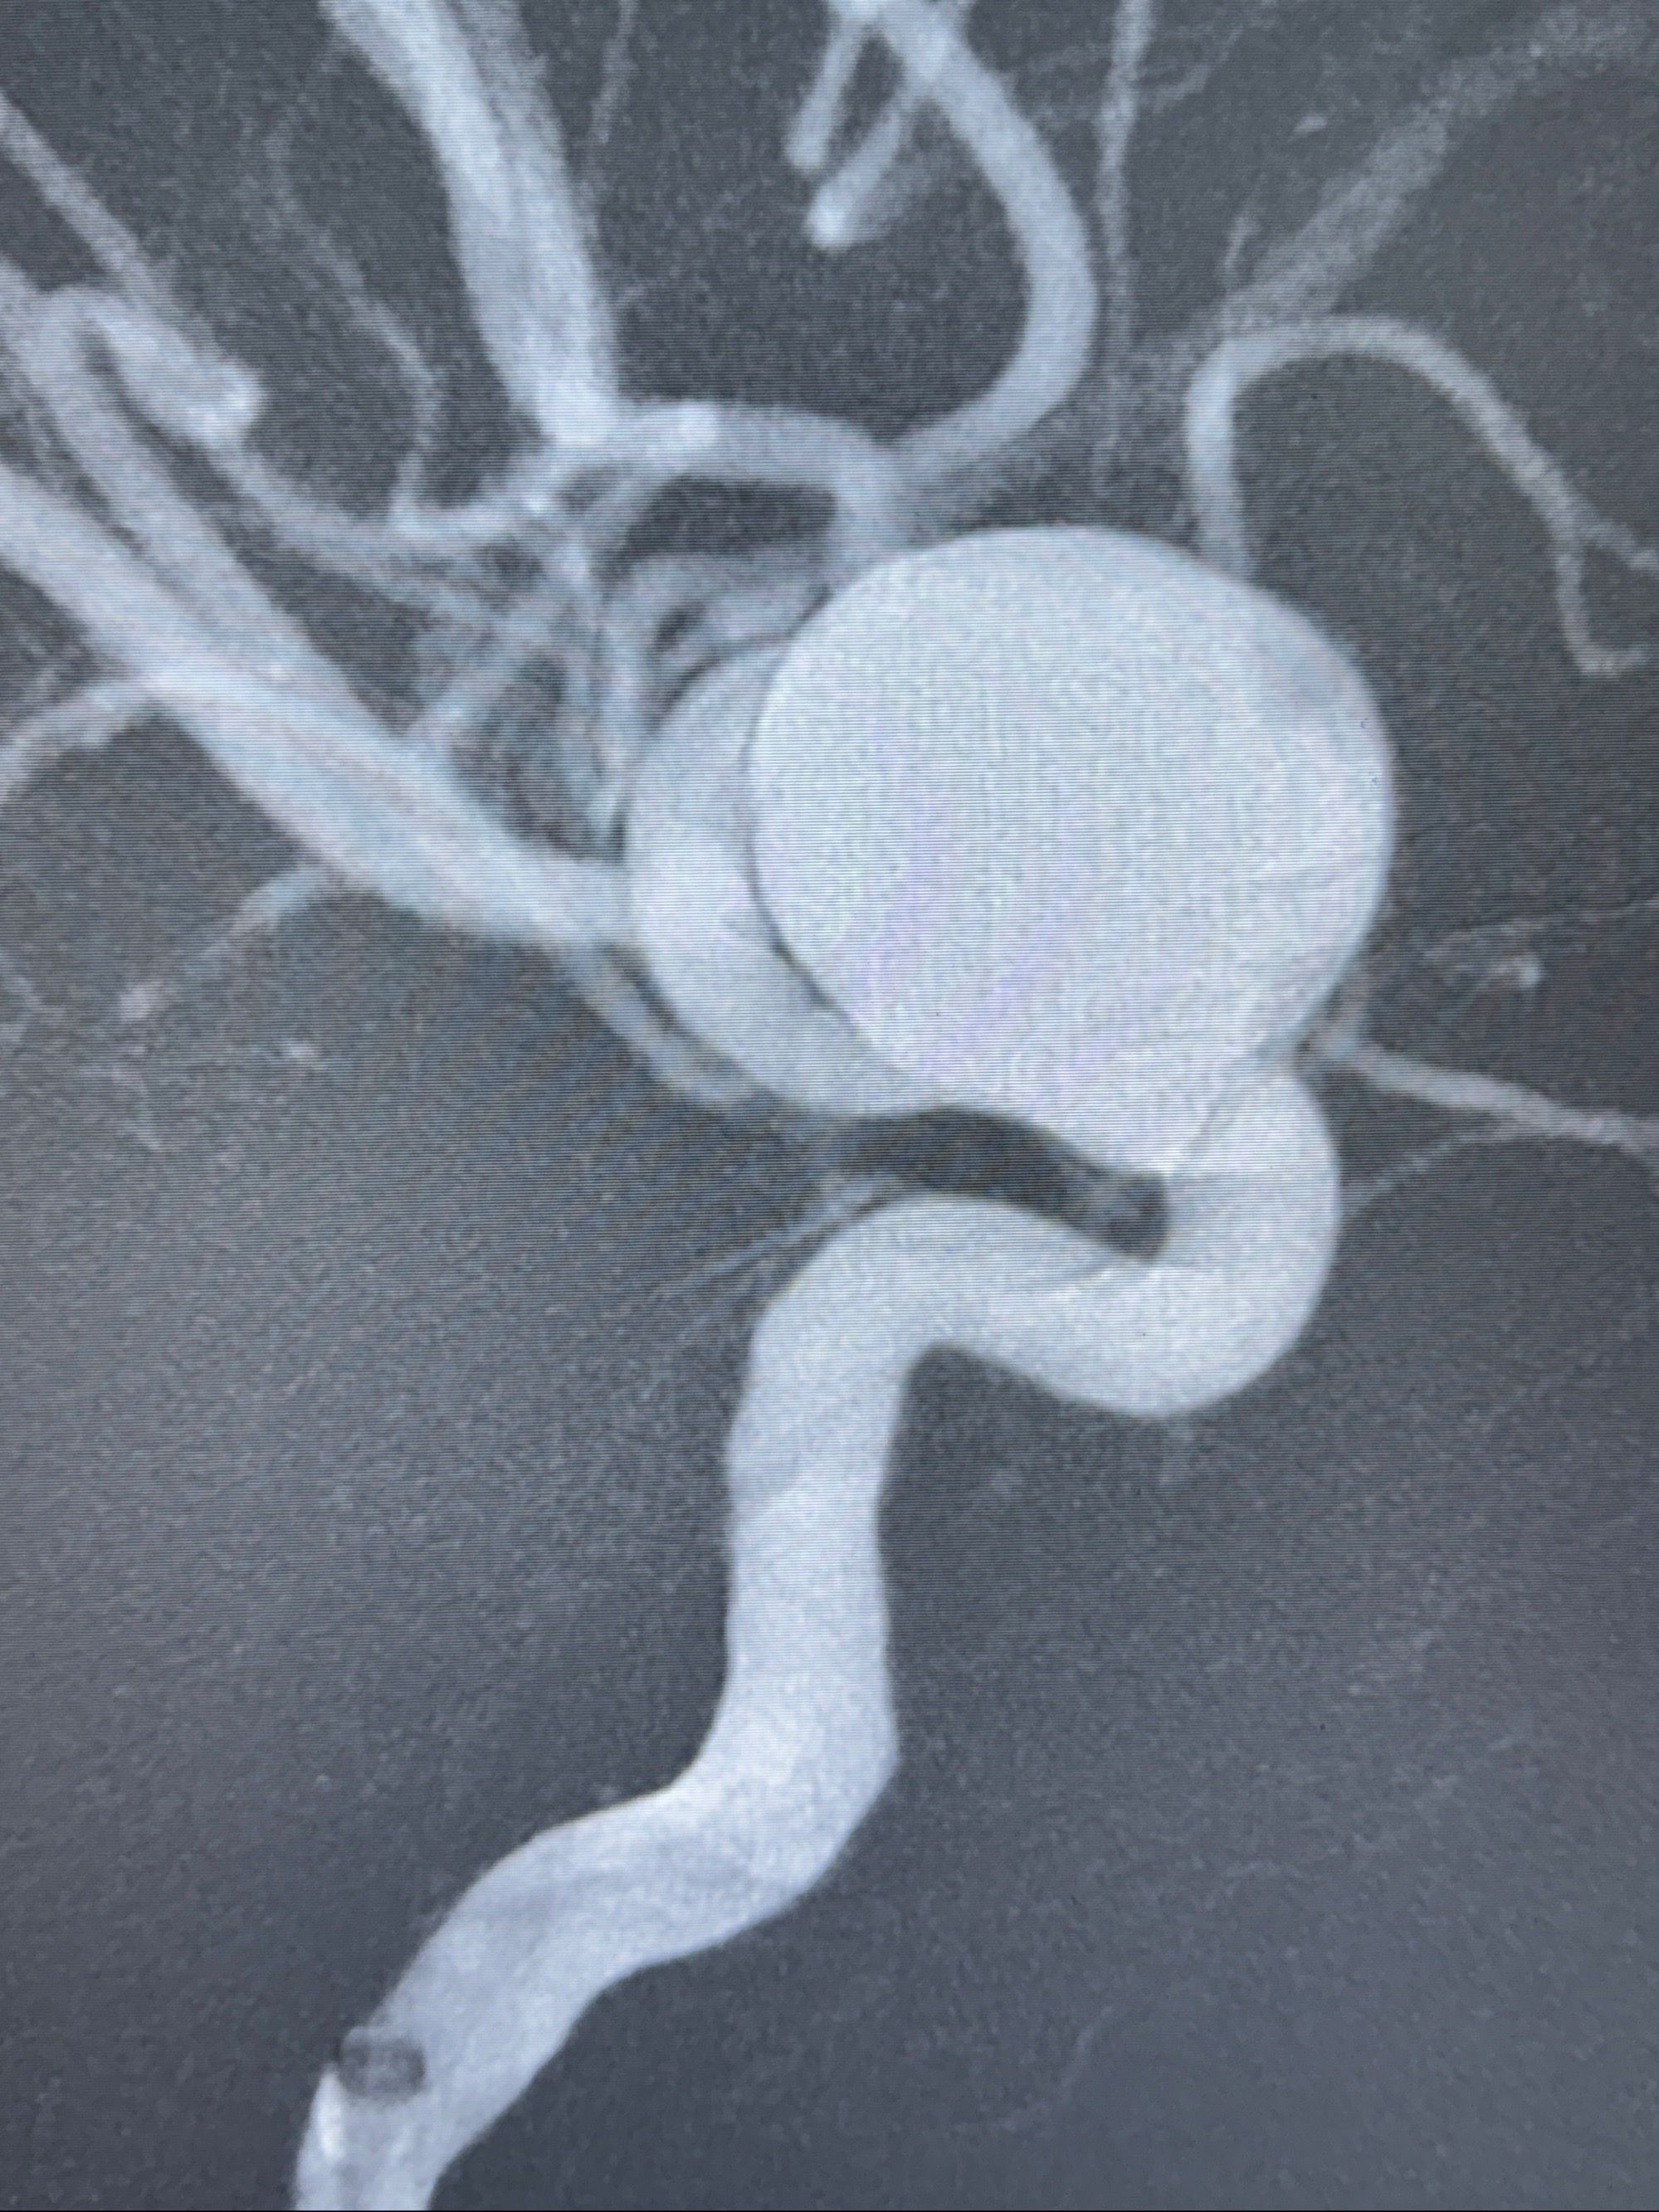

4.5-30mmTurbridge密网支架,于M1近心端打开

透视下支架释放满意

多角度显示支架打开情况

支架植入顺利,贴壁佳,支架内血流通畅,动脉瘤内血液滞留明显